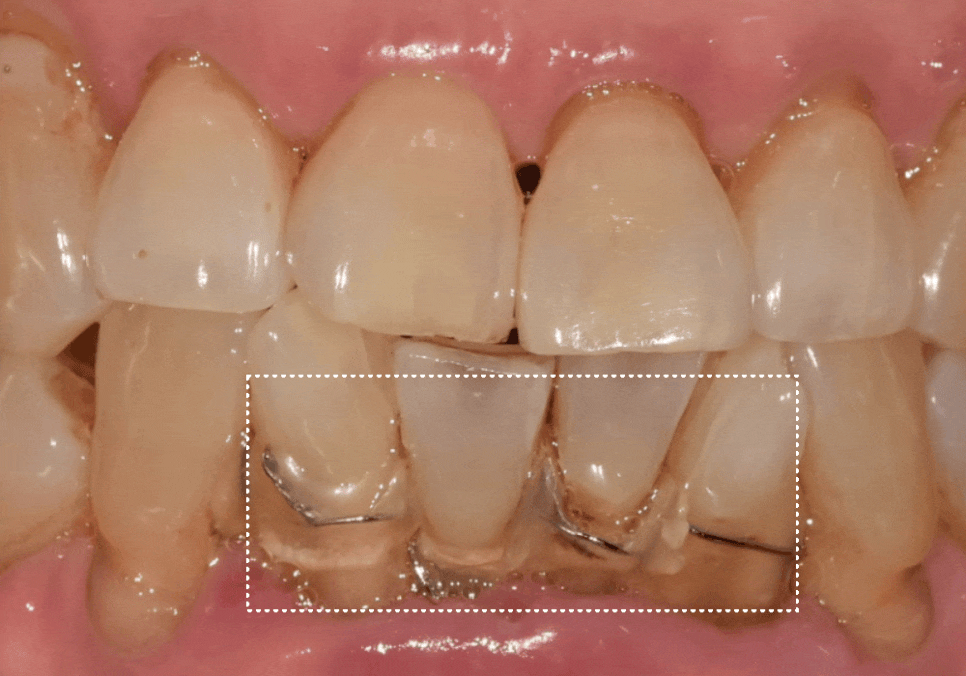

이 환자분은 과거에 아래

중앙 앞니(#31, 41)가 흔들리기 시작했을 때,

발치가 두려워 철사로

양옆 치아까지 넓게 묶어두셨다고 해요~

251022

당장 흔들림이 없으니

안심하고 오랜 시간을 보내셨지만,

정작 뿌리 끝에 박힌 염증 원인은

그대로 남아 있었죠.

결국 중앙 앞니에서 시작된 염증은

조용히 옆 치아(#32, 42)까지 퍼져나갔습니다.

내원 당시에는

이미 철사로도 감당할 수 없을 만큼

4개의 치아가 한꺼번에

심하게 흔들리고 있었고,

251028

주변 잇몸뼈가 광범위하게 녹아내려

결국, 앞니 4개를 모두 발치하고

임플란트를 진행했습니다.